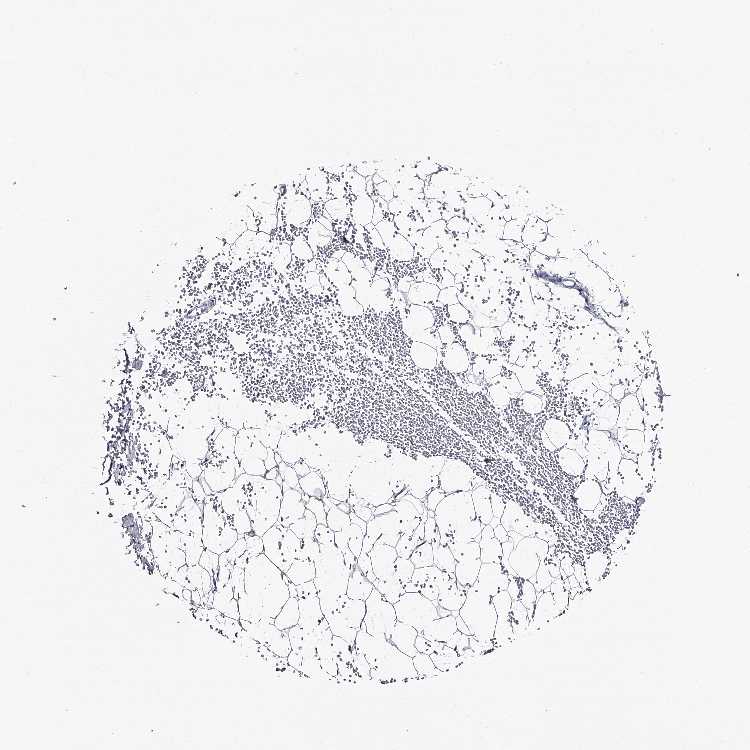

SOFT TISSUE 1 - Antibody stainingi

Antibody staining in the annotated cell types in the current human tissue is reported as not detected, low, medium, or high, based on conventional immunohistochemistry profiling in selected tissues. This score is based on the combination of the staining intensity and fraction of stained cells.

Each image is clickable and will lead to virtual microscopy that enables deeper exploration of all samples and also displays staining intensity scores, fraction scores and subcellular localization as well as patient and tissue information for each sample.

Antibody HPA038653Antibody HPA038654

Fibroblasts Not detectedNot detected

SOFT TISSUE 2 - Antibody stainingi

Chondrocytes LowNot detected

Peripheral nerve Not detectedNot detected